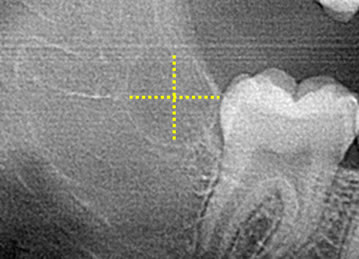

Zero3 technology has built-in controls to assure that the 3TBA procedure results in gently warming the targeted tooth bud (circled) from the center outwards to reduce the risk of adversely effecting adjacent tissue while clinically inducing 100% molar agenesis.

Zero3 technology accurately positions the center of the ablation in the center of the tooth bud.

Zero3 technology controls the 20-40 second ablation process to gently warm the targeted tooth bud tissue (circled) from the center outwards to clinically induce prescribed molar agenesis while not significantly effecting adjacent tissues.